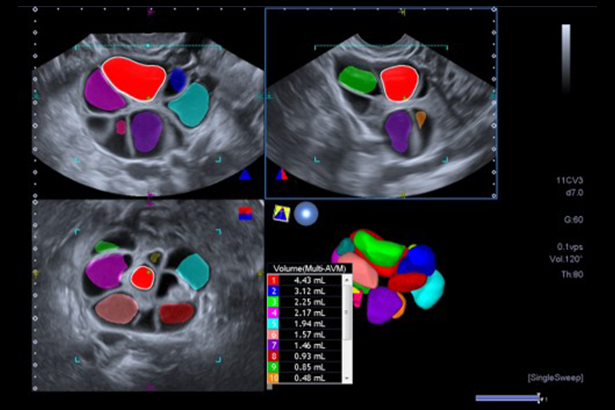

豐富的 Multi View 選項可以讓您看到各角度的高清顯示,幫助您理解解剖關系或占位的分布。